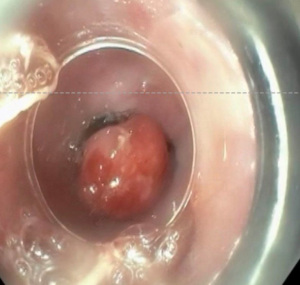

Endoscopic mucosal resection

EMR is the preferred initial treatment modality for nodular BE because it allows for comprehensive histologic analysis, given the fact that it preserves tissues rather than destroying it. This process begins by introducing either normal saline or epinephrine into the submucosal layer in order to elevate the lesion off of the muscularis propria. There are two methods that can be performed. The cap-assisted method targets the lesion and then retracts into the cap via suction, followed by resection via an electrocautery snare. The ligation-assisted method aspirates tissues via suction, followed by creating a pseudopolyp with a band ligation device and subsequent electrocautery (Figure 3). Although these techniques have similar outcomes, ligation-assisted is preferred because of its ability to resect several lesions with one kit, thereby making it more cost-friendly as well quicker (32).